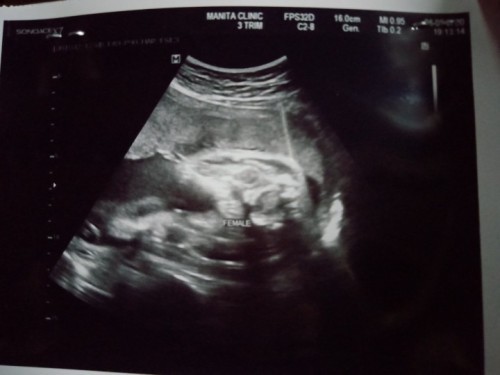

น้ำหนักลูก

อยากรุ้ค่ะว่าถ้าในใบซาวใม่บอกน้ำหนักลูกเราพอจะมีวิธีใหนที่พอจะรู้น้ำหนักบ้างค่ะ#ขอคำแนะนำหน่อยค่ะ